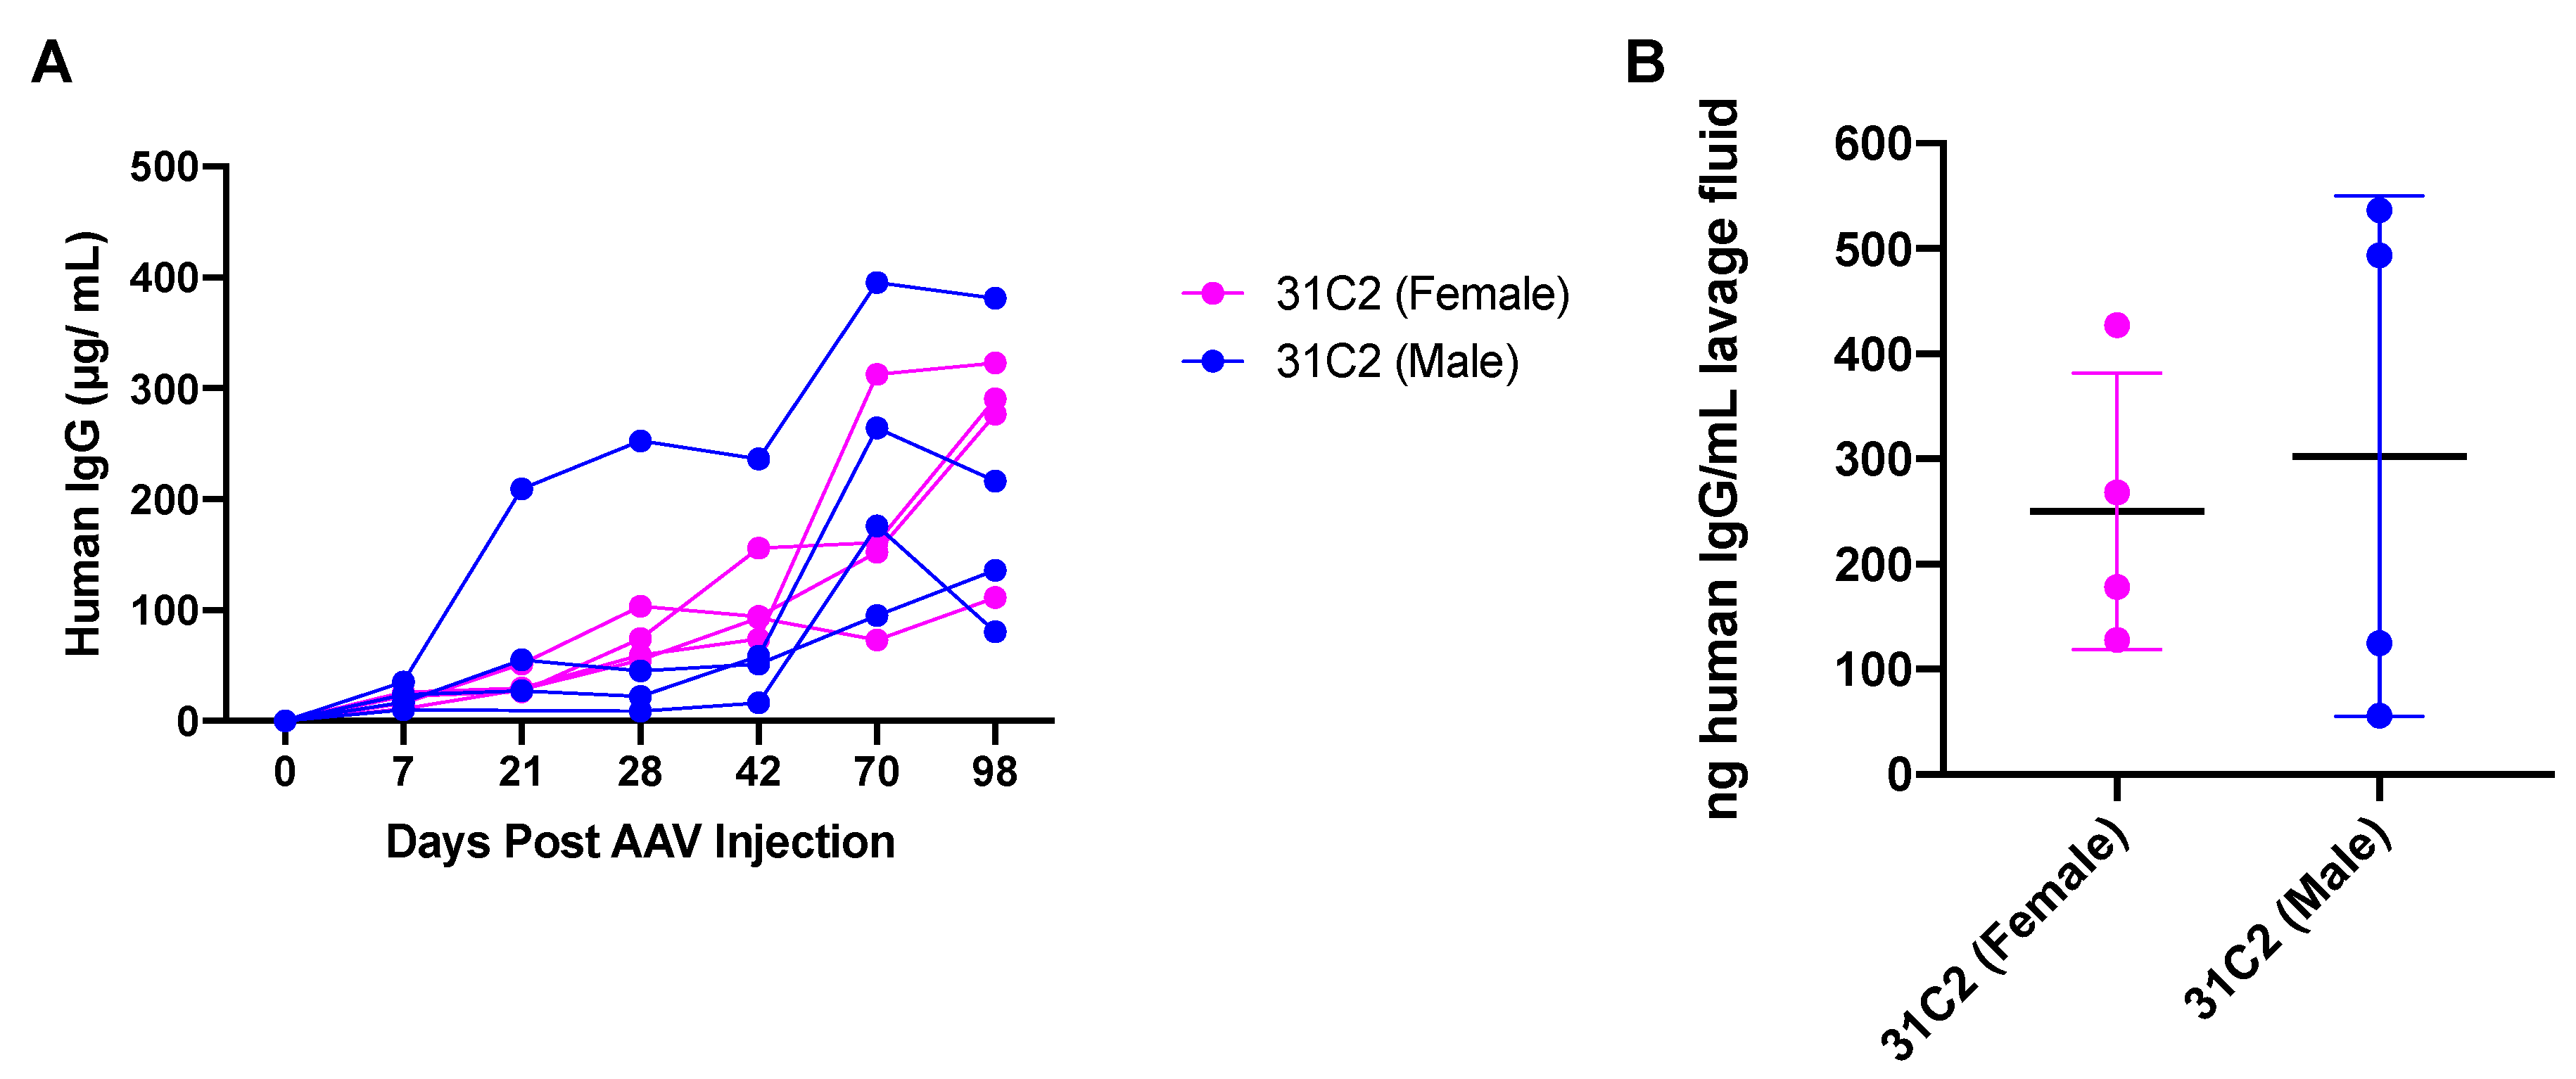

3.1. Confirmation of AAV6.2FF-31C2 Vector Expression

3.3. Safety and Tolerability of AAV6.2FF-31C2 in a Pediatric Ovine (Sheep) Model